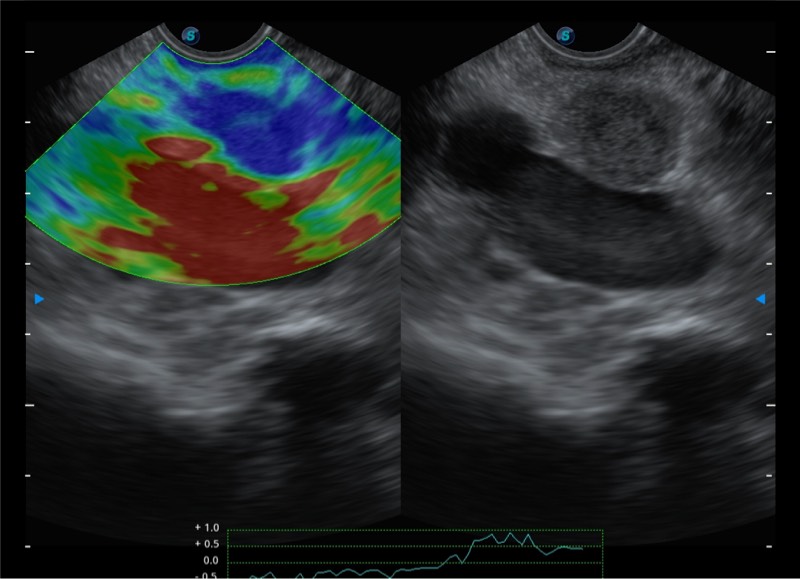

搭载百万级CMOS成像技术

及自主研发凸阵换能器,

可呈现优质的内镜和超声画面

基于二十年的超声技术积累,环球UG官网提供了最新一代的独立超声主机,在提供高质量图像的同时满足多学科使用。具备常见多普勒技术并提供弹性成像、声学造影等高端影像技术。新一代传感器具有更强的抗干扰能力并减少图像伪影。

4-12MHZ宽频输出